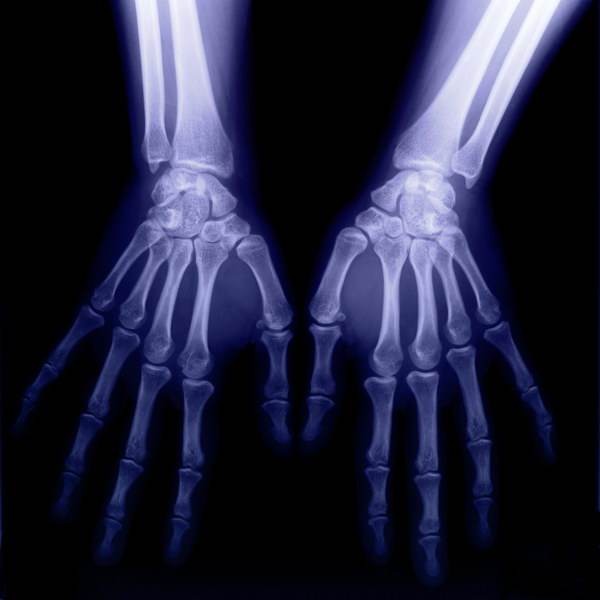

【X光:将人体骨骼投射到同一个平面上进行成像】

这个所谓的“看看”,又涉及到了X光的物理特性。医院当中X光检查的过程当中,主要用到了它的穿透作用、差别吸收、感光作用和荧光作用。其中,穿透作用和差别吸收主要用在检查这个环节,而感光作用和荧光作用主要用在检查结果的成像环节。

所谓“穿透作用”,就是X光能够穿人而过的本领。X光能够穿人而过,是因为它本身自带的能量很大,照在人体上时,仅有部分被人体吸收,大部分没被吸引就从人体的原子间隙穿过。“吸收差别”也是X光医学检查的重要因素,人体骨骼、肌肉在X光穿过时,对X光的吸收量有显著差别,这样当医疗设备射出的X光是衡量时,另一端感应器接收到的X光射线量就出现相对差别。

我们日常看到的X光片子,就是黑白一片。“一片黑白”当中隐藏的奥秘,正是来自于X光的感光作用和荧光作用。当X光照射到如磷、铂氰化钡、硫化锌镉等物质时,这些特定物质就会散发出荧光。荧光的强度与X光射线量成正比。医院中的X光检查设备用于感应检查结果的设置,正是用X光照到会发散荧光的特定物质做成。

这样一来,衡量的X光穿透过人体射线量已经出现差异,另一端结果感应器上的荧光强度也出现对应的差异。这种荧光强度的差异,再根据相关影像技术的转换,最终就呈现出片子上黑白颜色的差异。

骨骼对于X光射线量的吸收较大,所以片子当中骨骼的颜色几乎是白色,而肌肉的吸收量较小,所以呈现为黑色。

举两个例子说明一下医生怎么通过“黑白色差”判断病情:

一、比方说某患者小腿出现明显骨折,那他骨折处对X光的吸收量就与周边骨干呈现出明显对比,骨折处就会出现一条明显的黑色裂痕。再者,医生也会通过白色“画成”的骨干是否有异常变形做判断。

二、部分患者并非因为骨折去拍片,而是因为骨头里进了异物。要想通过手术取出来,首先得准确判断异物在骨干精确到毫米的位置。医生怎么判断呢?异物在骨头内对X光的吸收量不同,那个点就会与周边骨干呈现出明显色差,一般是白色的骨干当中出现明显的黑点。通过这一异常医生就可以锁定异物位置。